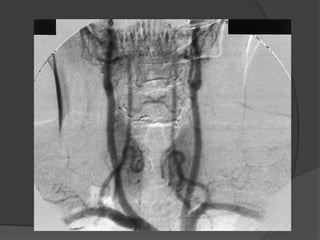

VASOS

Carótida externa.

 Proviene de la s arterias

carótidas comunes.

 Tronco braquio-cefálico.

 sub-clavia derecha.

 carótida común.derecha.

 Carótida común izquierda.

 Subclavia izquierda.

 Arco de la aorta.

CARÓTIDA EXTERNA

 Irriga la parte externa de la

cabeza y el cuello.

 Se dirige hacia arriba, perfora la

glándula parotidea y por detrás

del cuello de la apófisis condilar

de la mandíbula se divide en sus

ramas terminales.

 Temporal superficial

 Maxilar.